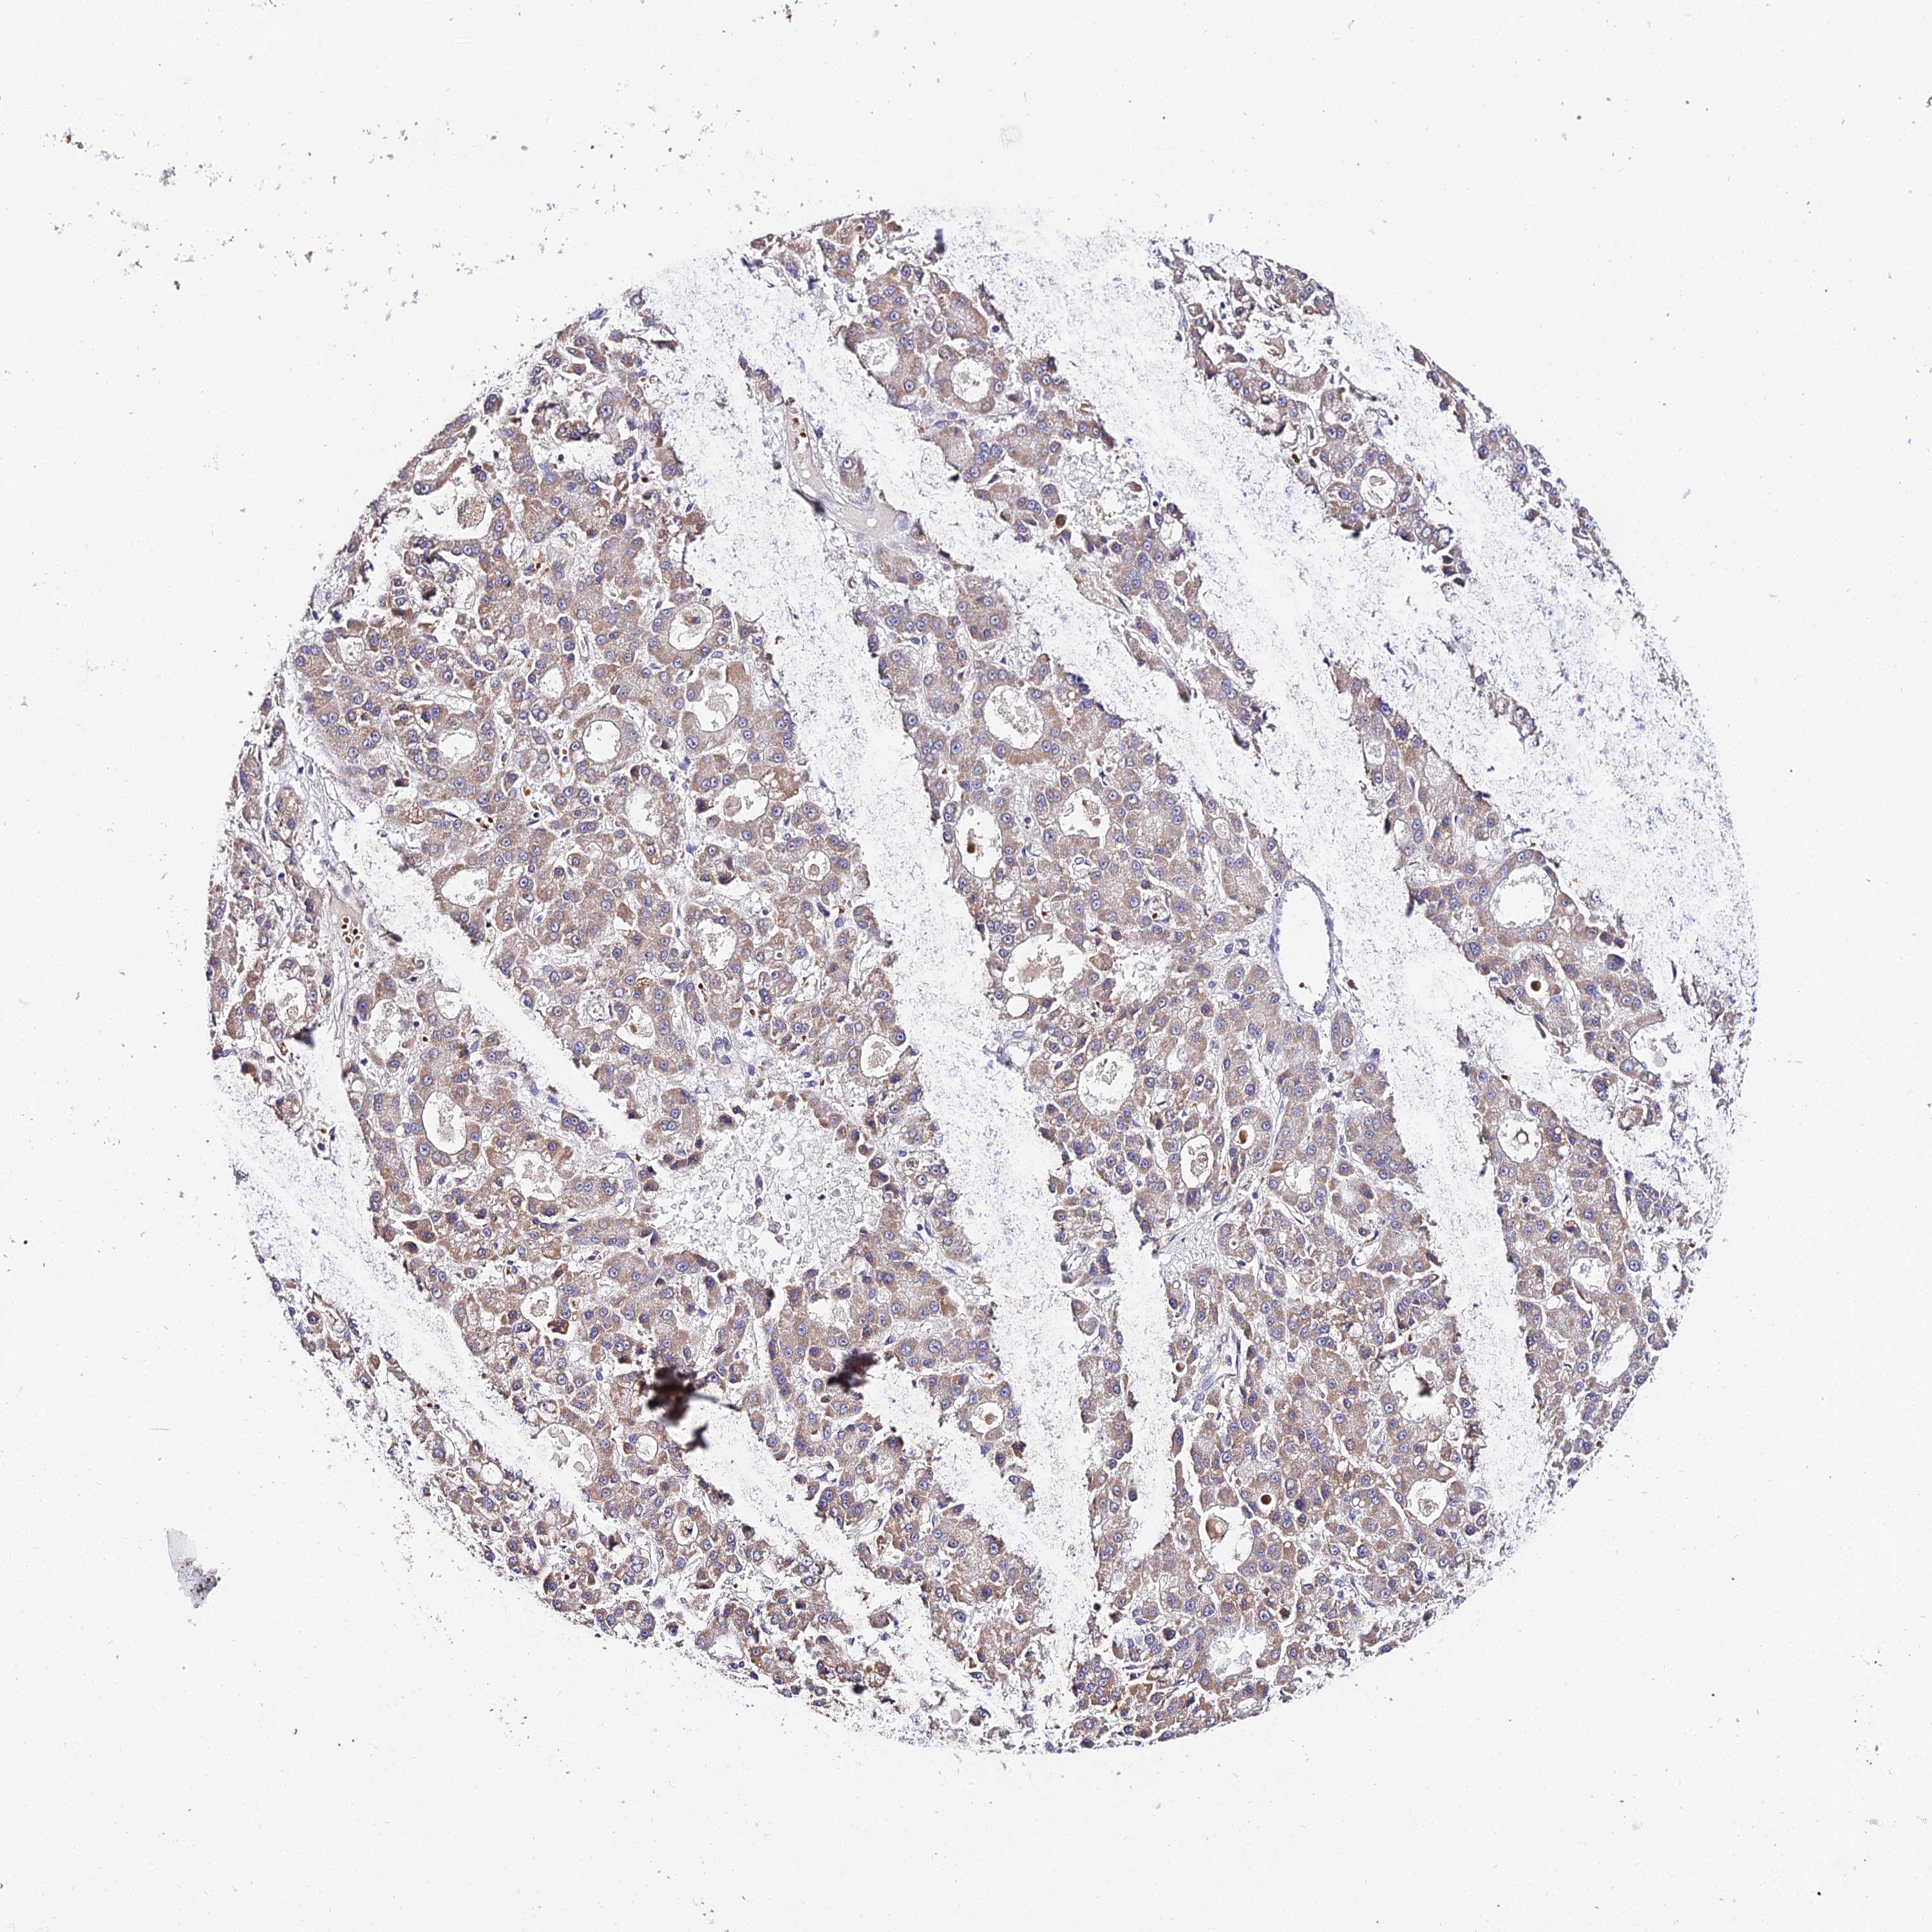

LIVER CANCER - Protein expressioni

A mouse-over function shows sample information and annotation data. Click on an image to view it in a full screen mode. Samples can be filtered based on level of antibody staining by selecting one or several of the following categories: high, medium, low and not detected. The assay and annotation is described here.

Note that samples used for immunohistochemistry by the Human Protein Atlas do not correspond to samples in the TCGA dataset.

Antibody stainingi

Antibody staining in the annotated cell types in the current human tissue is reported as not detected, low, medium, or high, based on conventional immunohistochemistry profiling in selected tissues. This score is based on the combination of the staining intensity and fraction of stained cells.

Each image is clickable and will lead to virtual microscopy that enables deeper exploration of all samples and also displays staining intensity scores, fraction scores and subcellular localization as well as patient and tissue information for each sample.

Antibody HPA042994

Staining

High

Medium

Low

Not detected

Intensity

Strong

Moderate

Weak

Negative

Quantity

>75%

75%-25%

<25%

None

Location

Nuclear

Cytoplasmic/membranous

Cytoplasmic/membranous,nuclear

Cholangiocarcinoma

Carcinoma, Hepatocellular, NOS